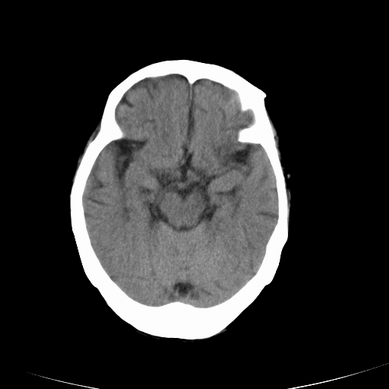

以下是引用jsgdoctor在2008-7-16 23:11:00的发言:[br]左侧大脑中动脉供血区脑梗塞